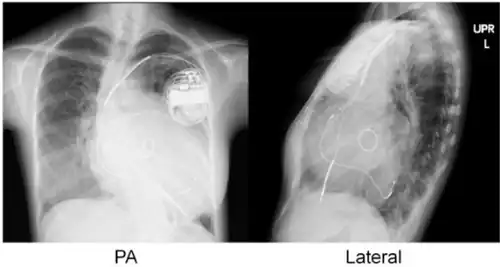

Cardiac resynchronisation therapy (CRT or CRT-P) is the insertion of electrodes in the left and right ventricles of the heart, as well as on occasion the right atrium, to treat heart failure by coordinating the function of the left and right ventricles via a pacemaker, a small device inserted into the anterior chest wall.[1]

- Atrial lead at the right appendage

- Right ventricular lead at the apex

- Left ventricular lead through the coronary sinus.[7]

CRT requires the placement of an electrical device for biventricular pacing, along with placement of (at least) two pacing leads, to facilitate stable left ventricular and right ventricular pacing. For all elements, the first stage of the process is local anaesthetic followed by incision to allow for approach from the appropriate vein. From here, the leads and device can be inserted.[1]

Device placement

The device is inserted in a subcutaneous pocket created by the surgeon, the choice of left or right side of the chest wall is determined mainly by the patient's preference or location of preexisting device. The device, similar to that of a traditional pacemaker, is generally no larger than a pocket watch and has inserts for the electrode leads.[1]